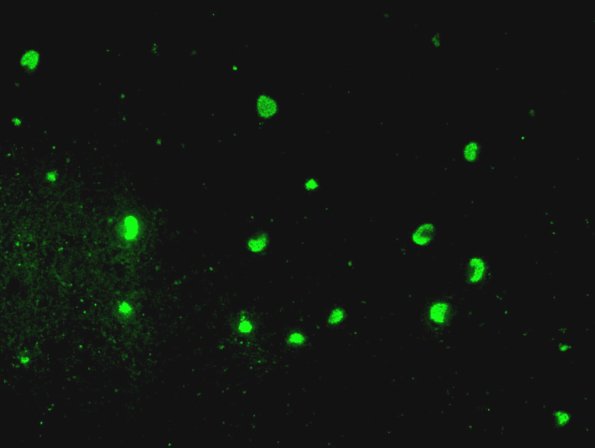

Neuronal Ceroid Lipofuscinosis (NCL)

2H8 NCL (Case 2) L14 Autofluorescence dentate 2